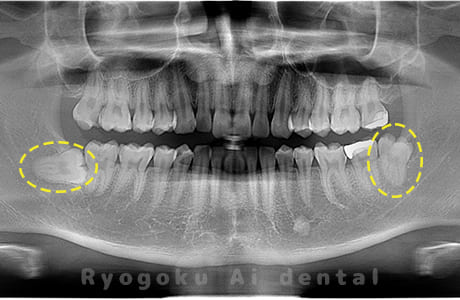

斜めに生えている親知らず

親知らずが斜めに生えて隣の歯にぶつかって圧迫してしまうタイプです。

このタイプが最も多いです。このタイプは虫歯になりやすいだけでなく、隣の歯を圧迫し、咬み合わせや歯並びに影響が出る場合もあるので抜歯をおすすめします。